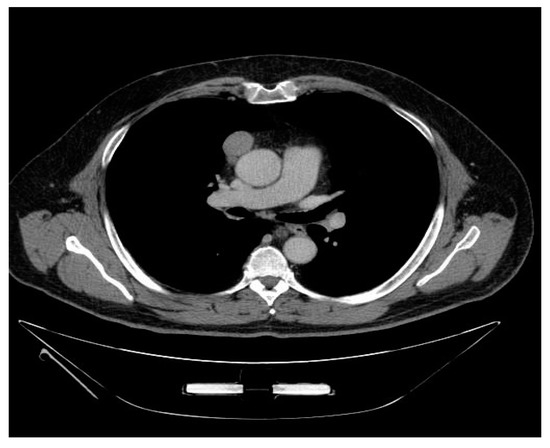

2.3. CT Scan Features and Image Interpretation

3.3. Correlation of CT Scan Parameters, Histology and Staging